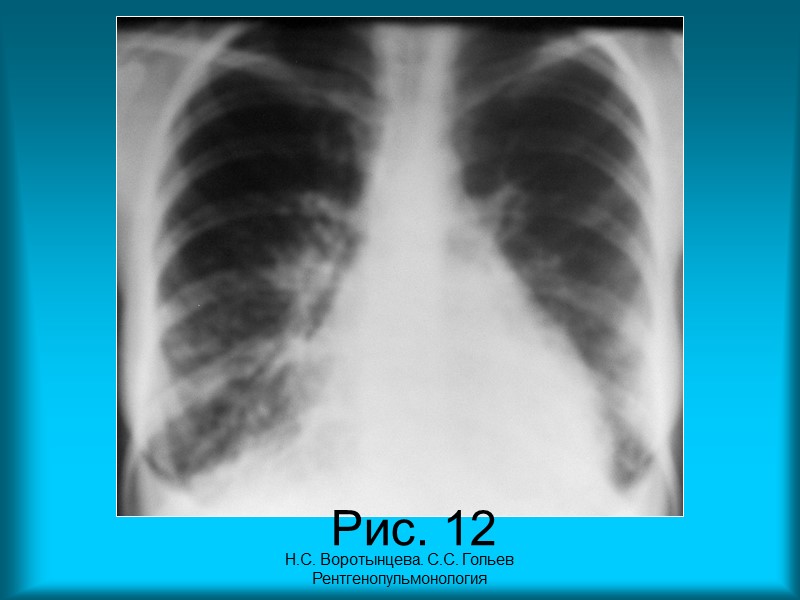

Н.С. Воротынцева. С.С. Гольев Рентгенопульмонология Пациентка Б. 28 л. Диагноз: Системная красная волчанка. Интерстициальный и альвеолярный отек легких. Рис. 12. Рентгенограмма органов грудной полости в прямой проекции. Грудная клетка бочкообразной формы. Верхние отделы легочных полей увеличены в размерах за счет повышенной пневматизации, а нижние – находятся в состоянии гиповентиляции. Прозрачность легочных полей снижена за счет обогащения и деформации легочного рисунка, мелкоочаговых теней и утолщения костальной плевры. Реберно-диафрагмальные синусы затемнены, контуры куполов диафрагмы не дифференцируются. Срединная тень расширена в поперечнике, контуры ее нечеткие, неровные.

Н.С. Воротынцева. С.С. Гольев Рентгенопульмонология Рис. 12